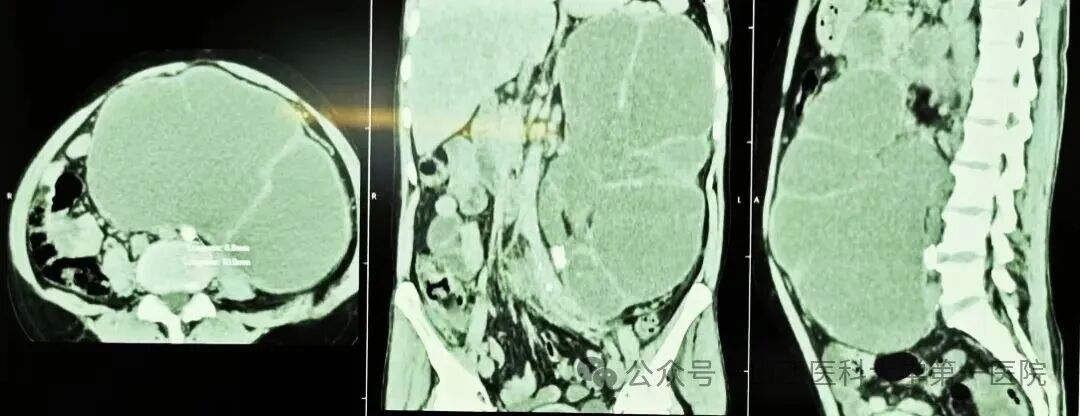

CT检查结果进一步揭示了病情的严重性:患者左侧肾脏已完全失去正常形态,转变为一个巨大的液性囊腔,肾实质被挤压得薄如纸片。李晶晶医生迅速判断:“这是重度肾积水合并感染,必须立即进行急诊引流,否则可能引发感染性休克,危及患者生命!”